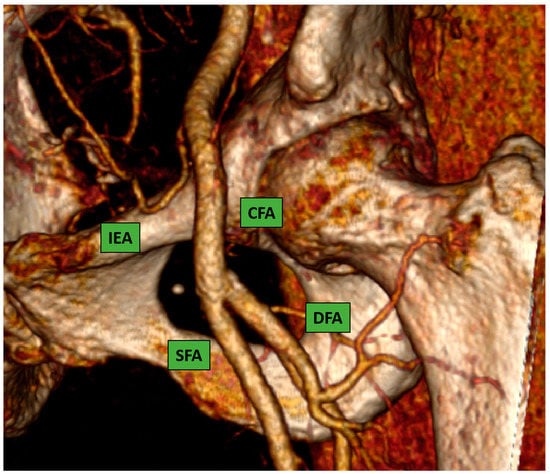

This is considered the preferred route in the majority of the procedures because most interventional cardiologists are very familiar with the transfemoral technique due to their experience with percutaneous coronary intervention. The CFA bifurcates into the superficial and the deep femoral artery; the correct puncture site should be at the level of the femoral bone head Figure 1 (ideally in the middle part of it) to have a compressible spot and to decrease the risk of retroperitoneal hemorrhage.

Figure 1.

Common femoral artery and bifurcation into superficial and deep femoral artery. 3D reconstruction image from computed-tomography scan (CT-scan).

Puncture sites not located in the CFA were associated with a higher rate of postcatheterization local vascular complications [7,8].